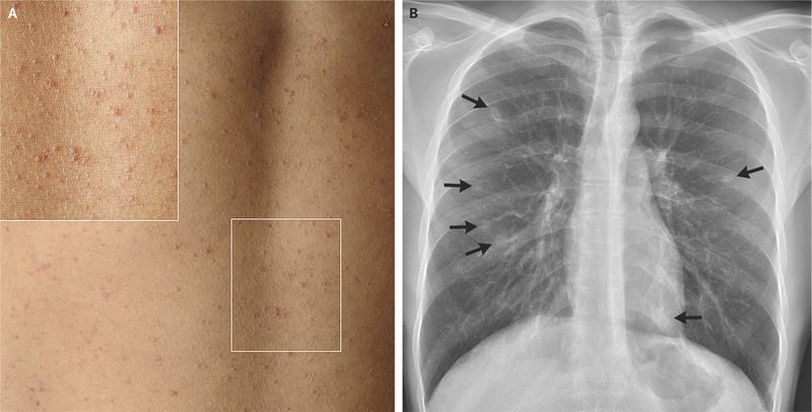

During a 3-month elective in Uganda, a 24-year-old Dutch medical student swam in the Nile River. Two months after his return, he presented to a clinic with a 7-week history of a nonproductive cough and malaise, as well as a 2-week history of diarrhea and nonpruritic rash. Physical examination and diagnostic testing revealed multiple small papules on the trunk (Panel A), eosinophilia (3.0Γ109Β eosinophils per liter), mildly elevated liver-function values, and several ill-defined nodular infiltrates on the chest radiograph (Panel B, arrows). Tests were positive for antibodies against schistosomal worms but not for antibodies against schistosomal eggs. Analysis of a skin-lesion biopsy specimen revealed nonspecific eosinophilic infiltrates without eggs. These findings support the diagnosis of acute schistosomiasis, or Katayama fever. Katayama fever is thought to be due to an immunologic response to the antigens present during the maturation process of the schistosomal worm. It typically manifests 2 to 10 weeks after exposure as fever, cough, urticarial rash, and fatigue, accompanied by eosinophilia and transient pulmonary infiltrates. Treatment with a single oral dose of praziquantel, preferably given after the acute stage, typically results in complete cure, as was seen in this patient.